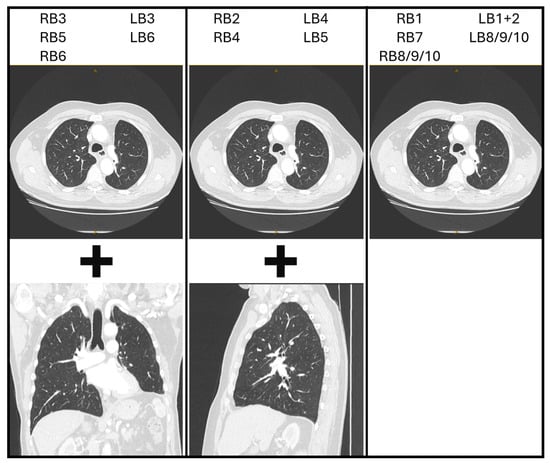

Figure 2. Potential CT image reconstructions for each segmental bronchus. RB = right segmental bronchi. LB = left segmental bronchi. For example, if navigating via the RB3 segmental airway, consider using axial images (with a horizontal flip ± 90-degree counterclockwise rotation) and coronal reconstructions.

Transformation (flipping and/or rotation) of the CT image is not essential, provided the bronchoscopist can maintain a spatial awareness of the anatomical directions as they draw the map. These anatomical directions are often marked on the edges of the CT images as well. Each bronchoscopist can therefore decide if they prefer to perform such transformations on the CT image or in their mind. However, it may be more instinctive if axial images are transformed in a manner that assists the bronchoscopist in imagining themselves navigating the CT images as if they were performing the bronchoscopy. Therefore, the authors suggest initially flipping the image horizontally to reflect the anatomical orientation as the bronchoscope enters the trachea, then rotating 90 degrees clockwise or counterclockwise for left and right-sided lesions, respectively. This reflects the rotation of the bronchoscope as occurs when the left or right main bronchus is intubated. Subsequent transformations may be natural for some users, such as flipping the CT image vertically for upper lobe lesions in the apical segments. It may also be helpful to use sagittal reconstructions for laterally projecting segmental airways and coronal reconstructions for anteriorly/posteriorly projecting segmental airways. Because the ostium of a segmental airway is rarely facing in a precise anatomical direction, consider either using the closest direction or a combination of axial and reconstructed CT images side-by-side. Potential combinations are suggested in Figure 2, although considering the individual anatomy on a case-by-case basis is most reliable.